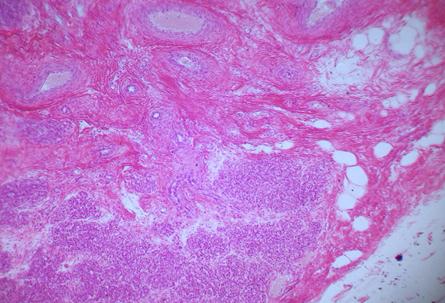

Фото. 3.3.2. Паращитовидная железа на задней поверхности щитовидной железы, погруженная в ее капсулу. Гем.-Эоз.

Малое увеличение. (Ув.10х7)